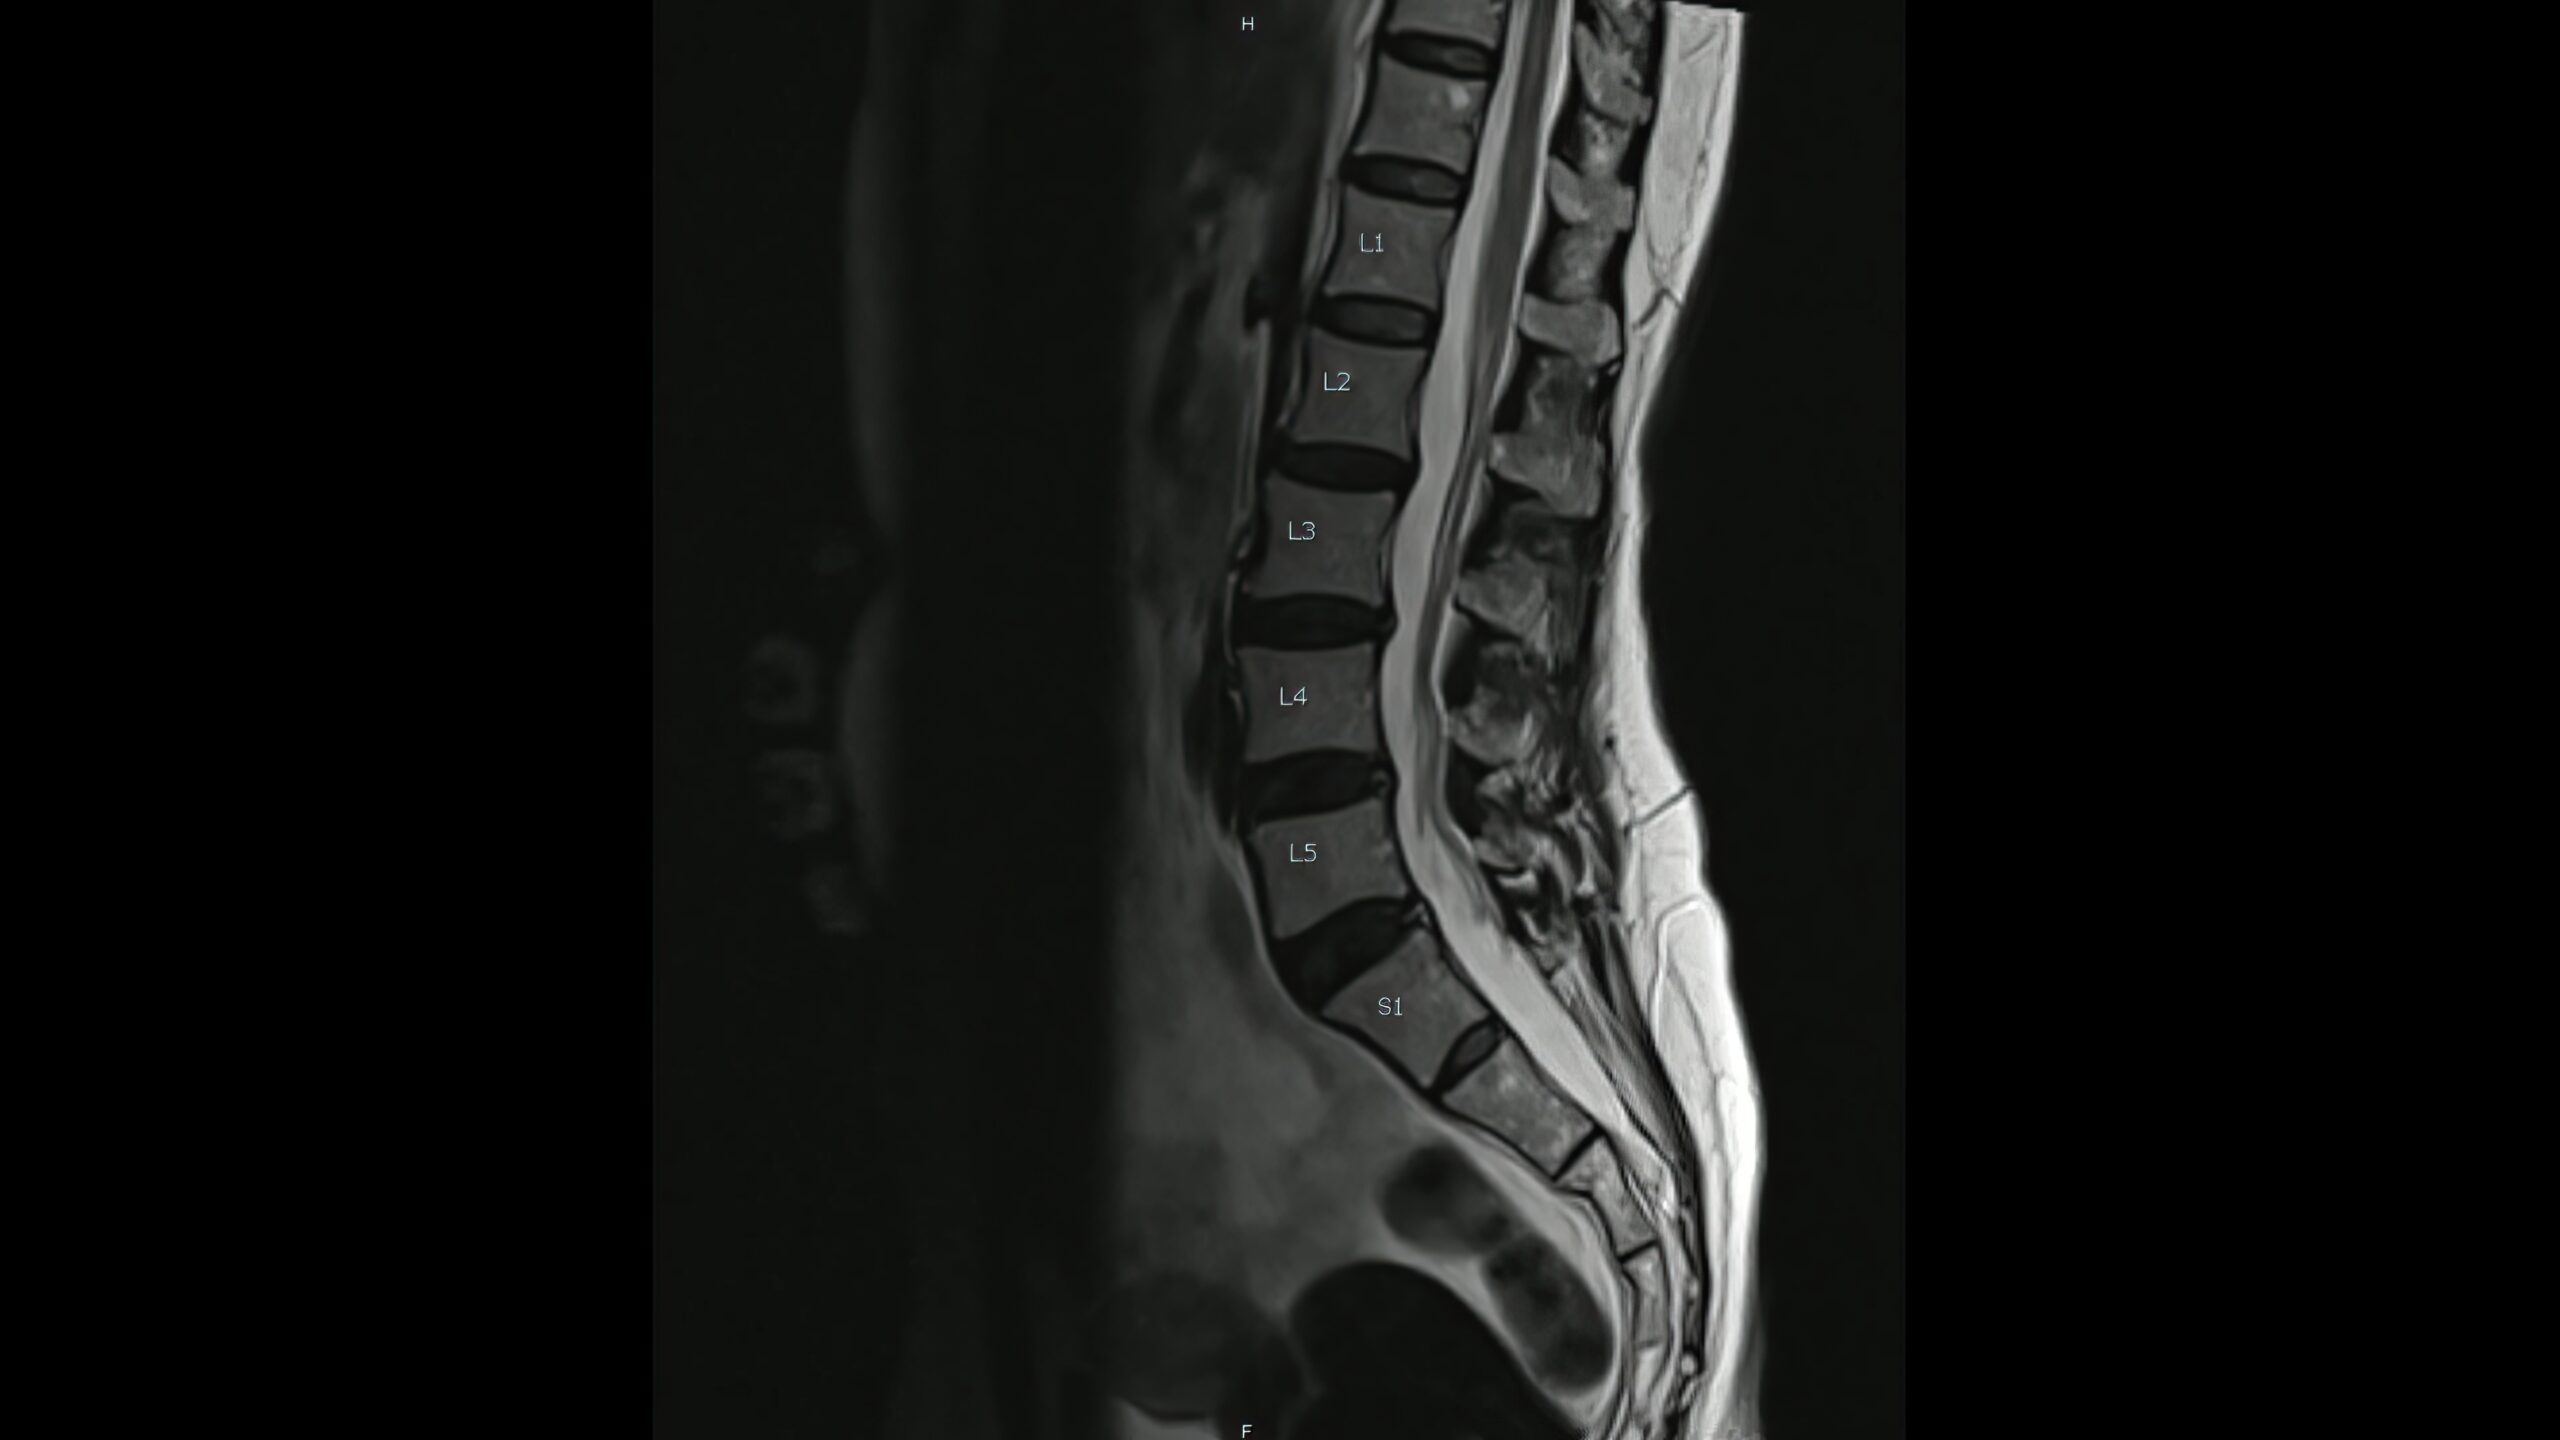

Assessment: Urgent MRI to confirm compression and identify the cause; blood tests; early antibiotics if abscess is suspected.

Assessment: MRI with contrast, CSF (including antibodies), targeted bloods (B12, copper, autoimmune/infectious screens) and, where helpful, evoked potentials.

Assessment: Clinical pattern, MRI to exclude compression, and genetic testing with counselling; EMG/NCS to assess for co-existing neuropathy.

Yes—MRI is the key test to confirm cord involvement and decide on urgent treatment.